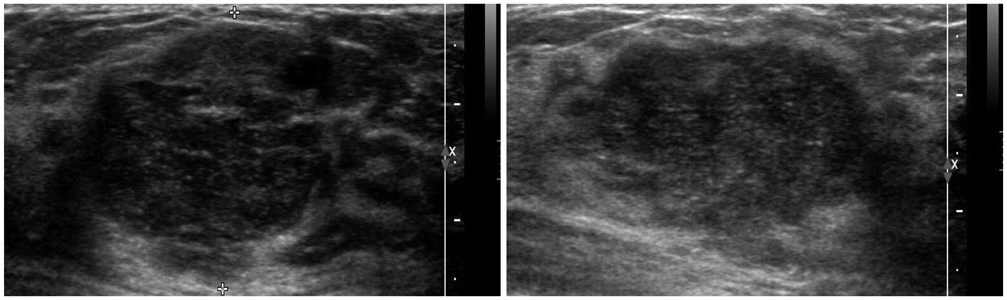

- The purpose of this study is to review various breast diseases in children and adolescents and to illustrate the sonographic findings. We reviewed the cases at our institution in order to identify breast disease in children and adolescent patients who underwent sonography and mammography. Breast disease in children and adolescents included developmental disturbance, infection, benign tumors and inherent defects. In contrast to adults, the radiologic findings of malignant breast conditions in pediatric populations have rarely been reported; however, we show ductal carcinoma in situ with juvenile fibroadenoma and rhabdomyosarcoma. During childhood and adolescence, the recognition and correct identification of physiologic breast development and specific lesions in breast entities on radiologic findings is most helpful in identifying and characterizing abnormalities and in guiding further investigation.